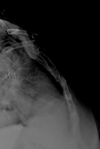

Pared torácica

Malformación costal